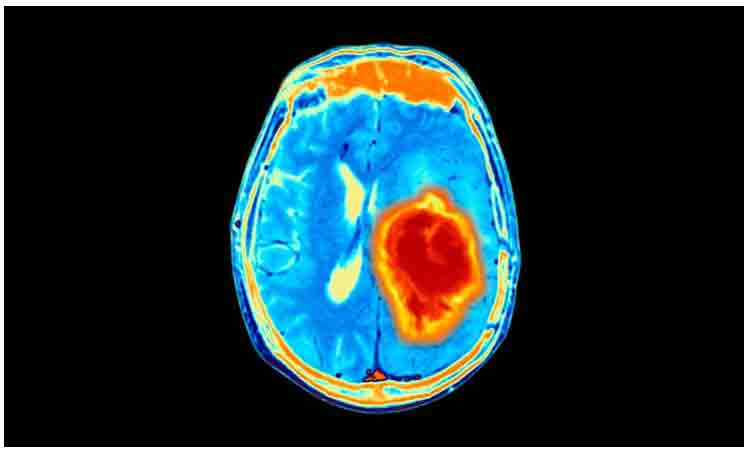

World Encephalitis Day | దోమల వల్ల వచ్చే ప్రాణాంతకమైన వ్యాధి మెదడువాపు. దీన్ని ఇంగ్లీష్లో ఎన్సెఫలైటిస్ అని పిలుస్తారు. ఈ వ్యాధి కారణంగా మెదడులోని నాడీ కణాల్లో వాపు ఏర్పడి వాటి పనితీరులో అవరోధాలు ఏర్పడ